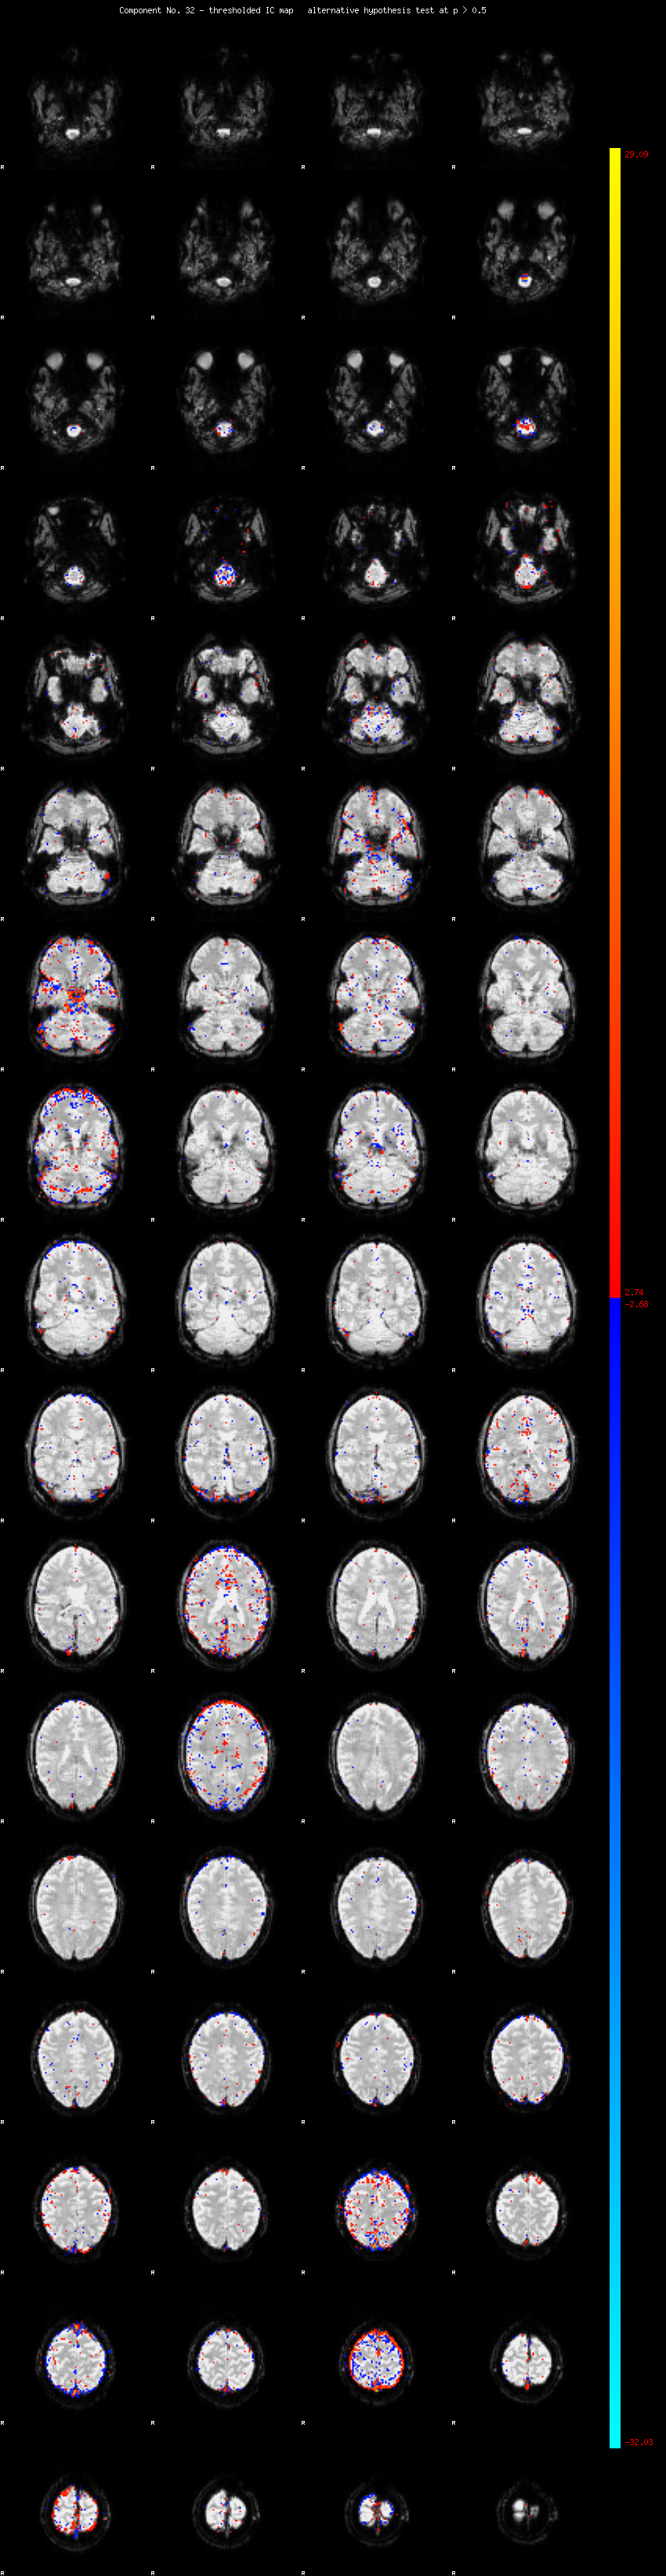

MELODIC Component 32

1.20 % of explained variance;     0.79 % of total variance

MMfit